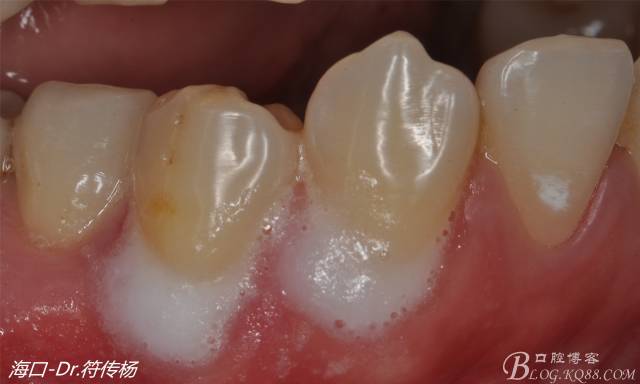

從病例圖片我們可以看到44牙頰側(cè)牙齦出現(xiàn)明顯萎縮

術(shù)前評(píng)估:退縮的齦緣在MGJ冠方 近遠(yuǎn)中牙槽嵴頂高度正常 屬于Miller -Ι類牙齦退縮 所有術(shù)后可以完全覆蓋